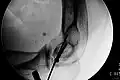

-

Klassische Zuggurtung einer Patellafraktur -

Erweiterte Zuggurtung einer Patellafraktur (mit K-Drähten) -

Eine Bimalleolarfraktur im seitlichen Röntgenbild … -

… und von vorne … -

… mit Zuggurtung am Innenknöchel und Platte am Außenknöchel versorgt